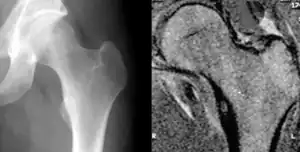

| Osteoid osteoma of the trochanter minor: X-ray and MRI with marked sclerosis around the nidus | |